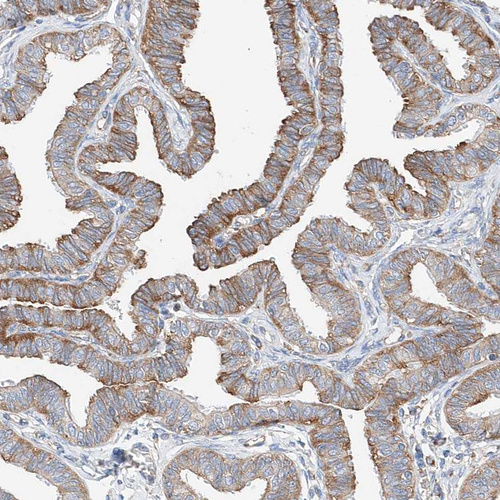

Immunohistochemical staining of human fallopian tube shows moderate membranous positivity in glandular cells.